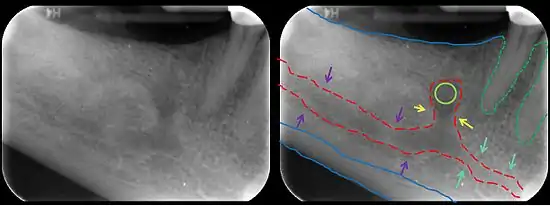

The mandibular incisive canal (indicated here by coral green arrows) continuing anteriorly (to the right) from the mandibular canal (purple arrows) after the mental foramen (light green circle).

The mandibular incisive canal is a bilaterally paired bony canal within the anterior portion of the mandible that extends from the mental foramen (usually) to near the ipsilateral lateral incisor teeth.[2]

The inferior alveolar nerve splits into its two terminal branches within the mandibular canal: the mental nerve (which exits the mandible through the mental foramen), and the incisive nerve which represents an anterior continuation of the inferior alveolar nerve and continues to course within the mandible in the mandibular incisive canal. The incisive nerve provides innervation to the mandibular first premolar, canine and lateral and central incisors.[2] The incisive nerve either terminates as nerve endings within the anterior teeth or adjacent bone, or may join nerve endings that enter through the tiny lingual foramen.

The incisive canal is typically found within the middle third of the mandible in an apico-coronal dimension, reaching the midline 18% of the time.[3]